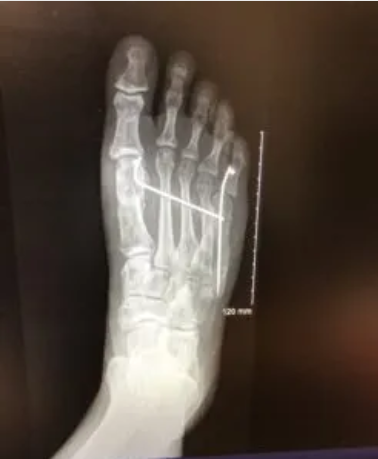

杰米多年受不明原因的足部疼痛困扰,历经三年多国求医无果,最终在paley研究院获得新生。拉姆医生凭借精湛医术,通过 X 光片精准诊断出短跖骨症、小趾囊肿及跖趾关节炎三重病症。在paley团队的全程护航下,经过两次针对性手术及八个月康复护理,杰米彻底摆脱疼痛,重获健康。这一案例彰显了帕利研究院在骨科畸形矫正领域的全球领先实力与人文医疗理念。